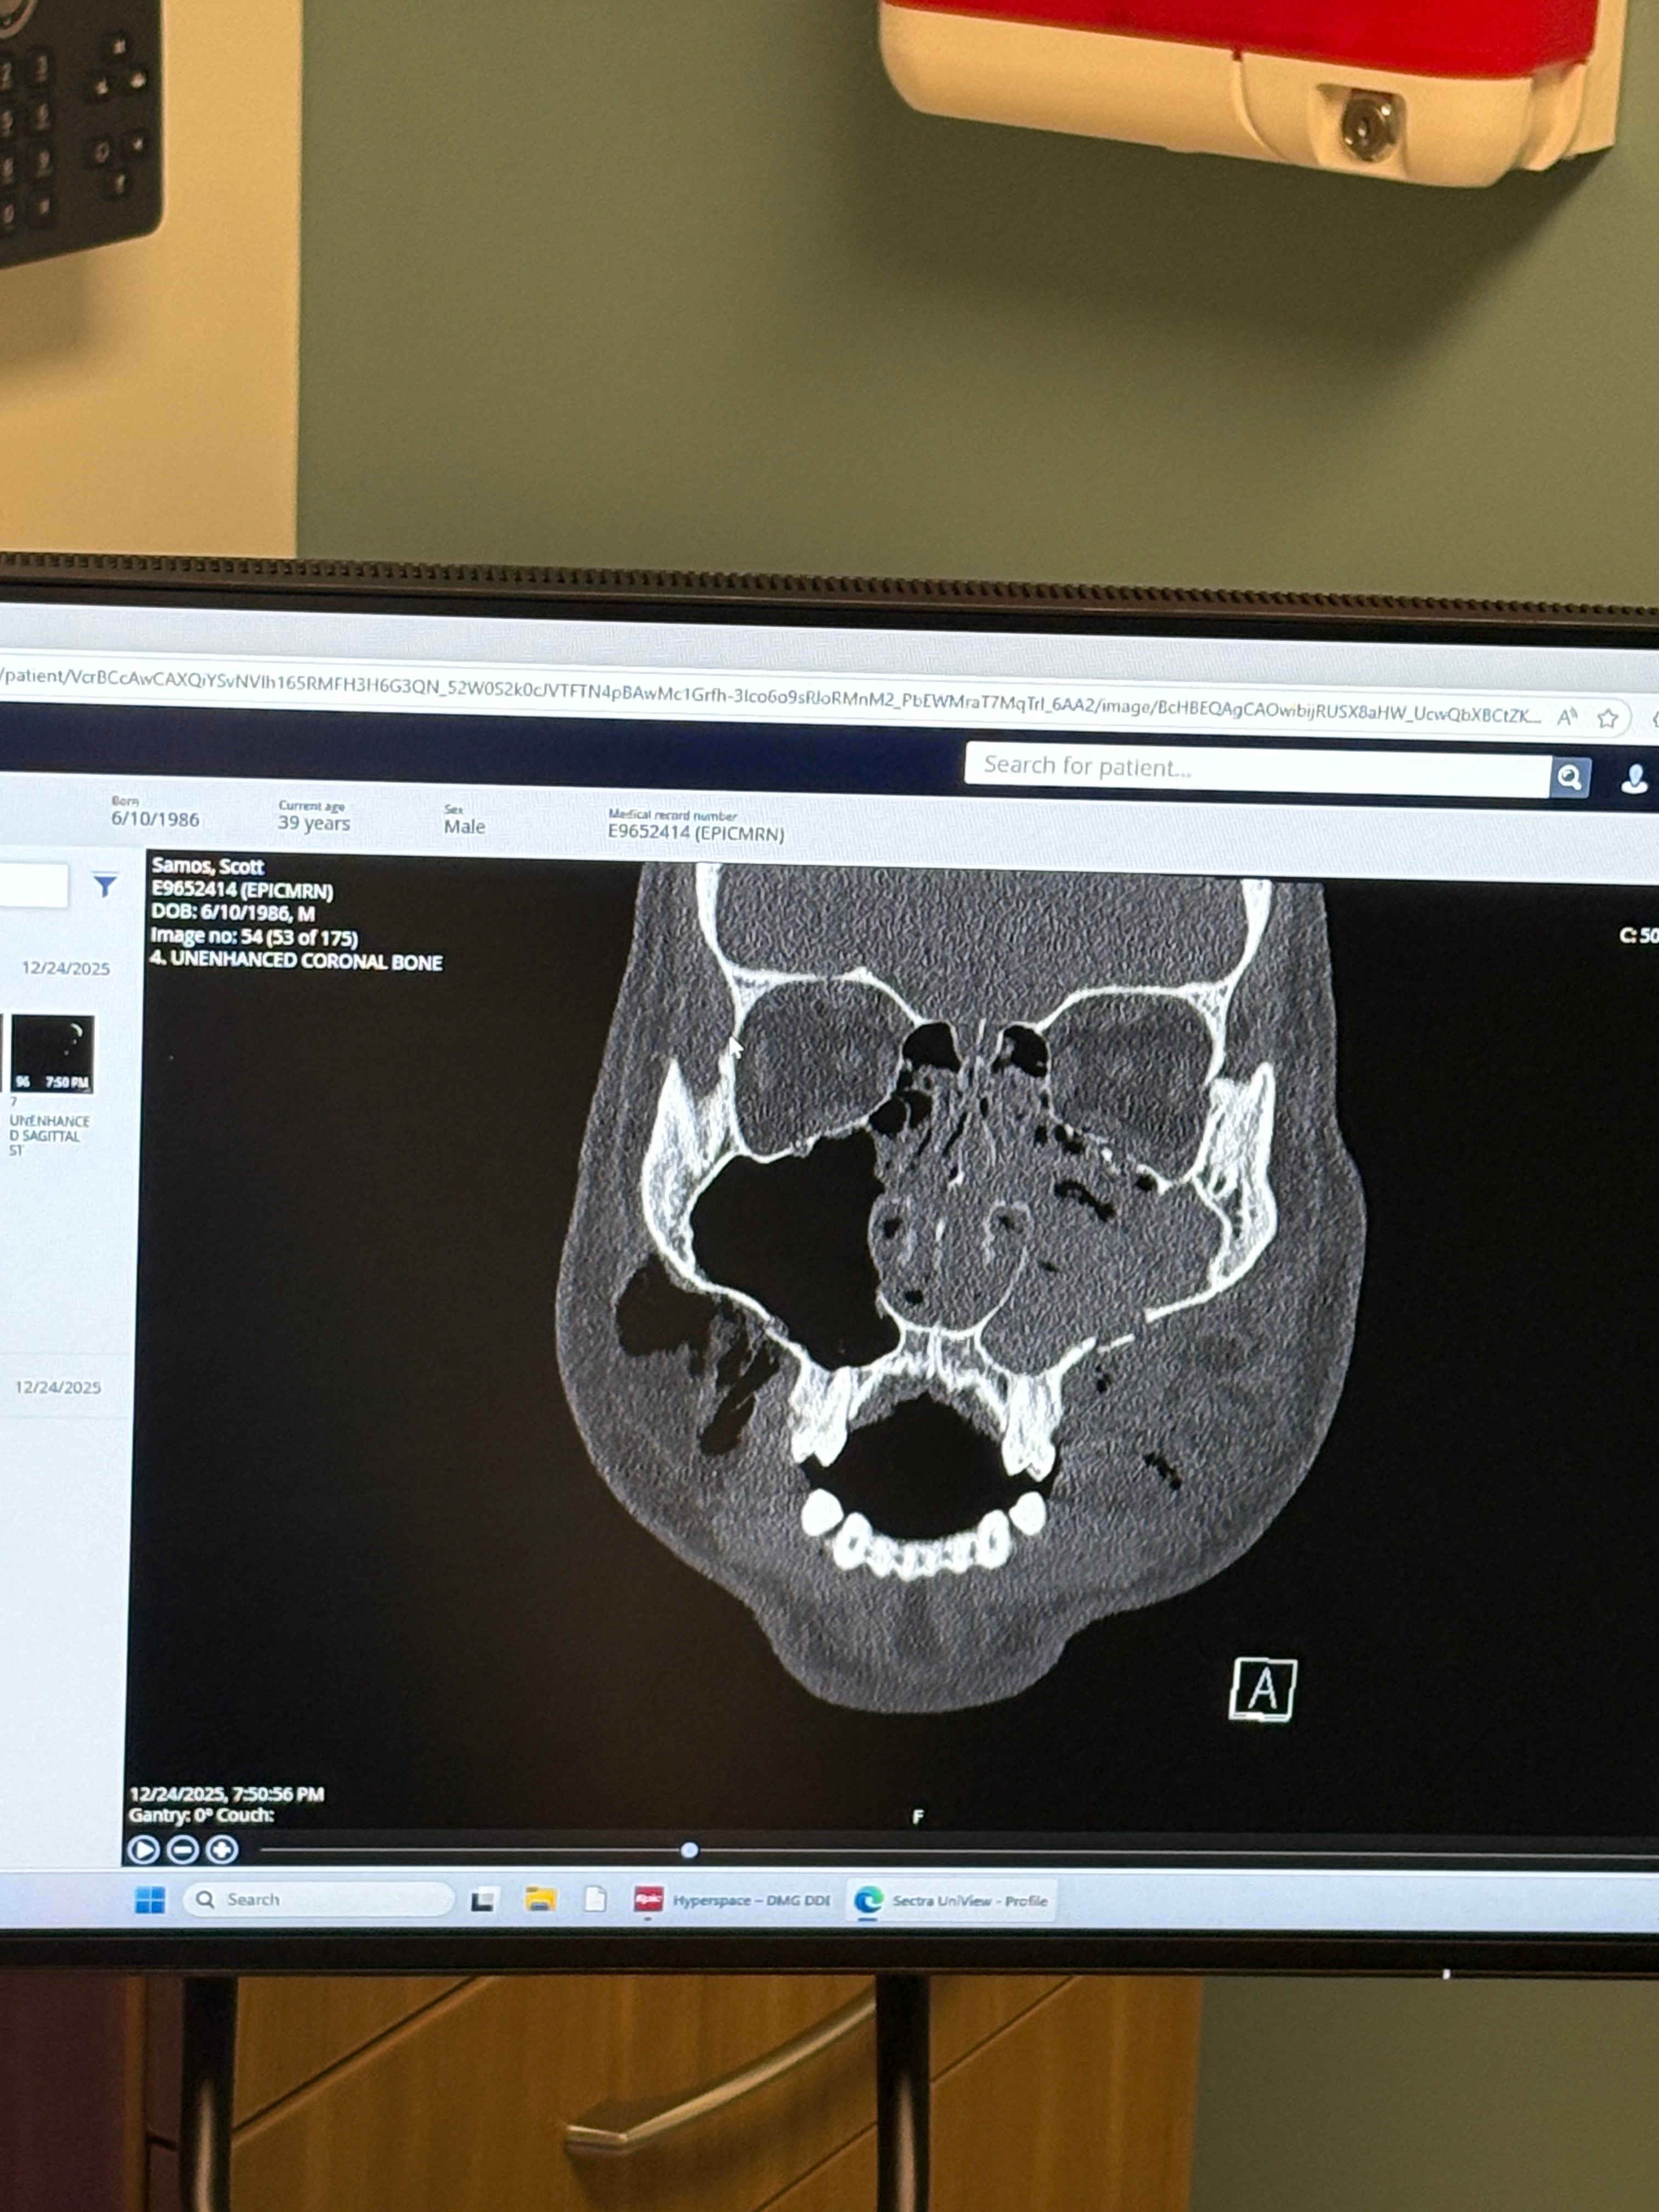

On Christmas Eve, my brother was the victim of a violent assault and robbery. As a result, he suffered multiple fractures to his face that required immediate medical care. This has been an incredibly traumatic experience—physically, emotionally, and financially.

Right now, Scott is focused on healing, but the recovery process will be long and painful. He is facing significant medical expenses related to emergency care, imaging, specialist visits, and potential surgeries, along with medications and follow-up appointments. On top of that, the assault has left him unable to work during his recovery, creating additional financial strain.

Recently, we saw an oral surgeon to fix his bite, as the impact of the injury caused his teeth to shift immensely, limiting the kinds of foods he can eat and his voice. Scott is slowly integrating soft foods but has been on a mostly liquid diet. Surgery for his jaw will take place anywhere from 1-3 months from now; requiring them to re-break his upper jaw to get his alignment back into place. Healing time will take about 1-3 weeks.